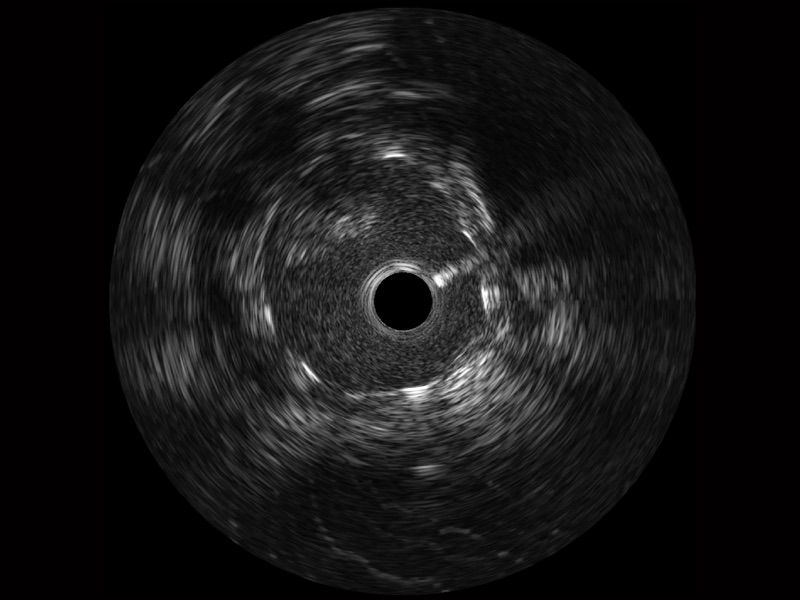

临床图

远场分支血管及导丝

支架内血栓

组织脱垂